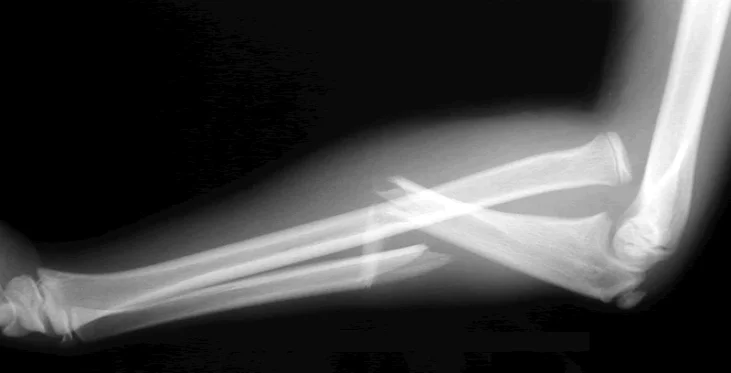

Monteggia Fracture/Dislocation

- Fracture of the proximal third of the ulna with dislocation of the head of the radius

- Dislocated head of radius missed if two joints are not included on the x-ray

- “Fracture of necessity”. Treated by:

- Open reduction and internal fixation of ulna

- Closed reduction of head of radius

- +/- fixation